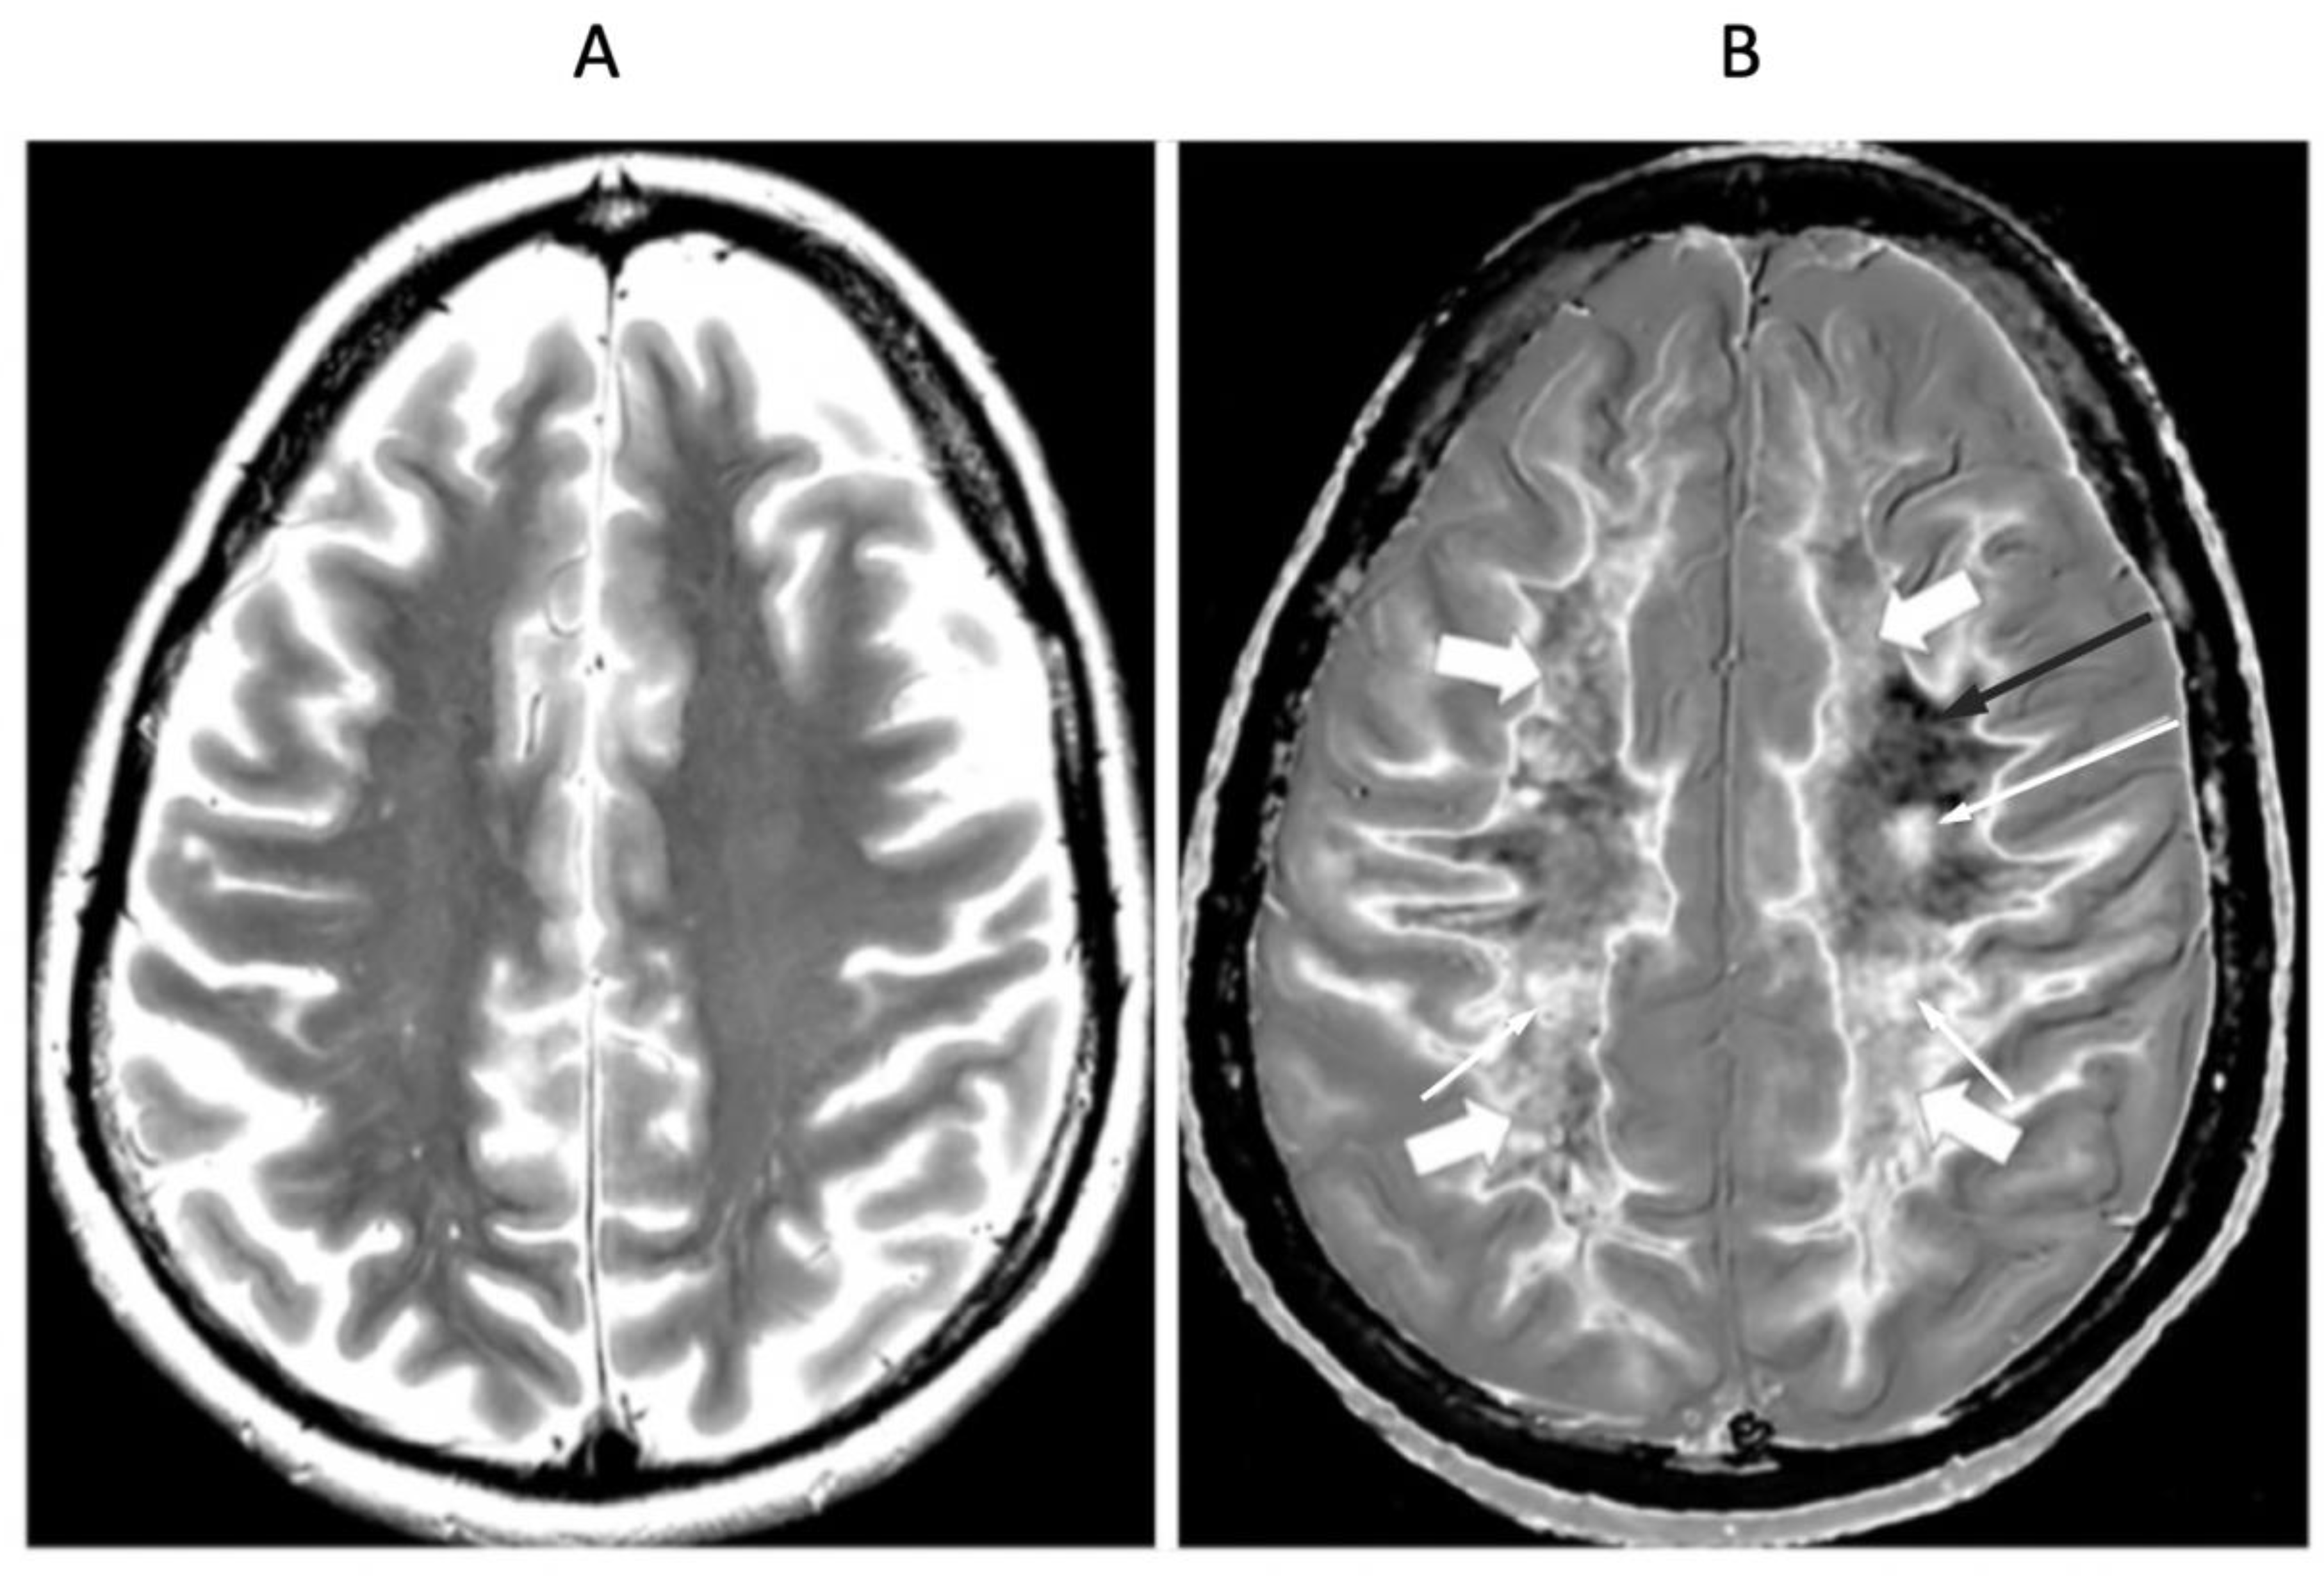

Figure 15.

41-year-old female patient with MS in remission. 2D T2-wSE (A) and narrow mD dSIR (T1-BLAIR) (B) images at the same level. No abnormality is seen in (A). A focal lesion is seen in (B) (long narrow white arrow) and the cortico-spinal tracts show a high signal (short narrow white arrows). In addition there is patchy increased signal in white matter (short thick white arrows) with only a small region showing a normal or near normal low signal appearance (long black arrow). High contrast and high spatial resolution contrast are seen at the boundaries between normal white matter and normal gray matter in (B). These features are less obvious in areas where the white matter has abnormal high signal.